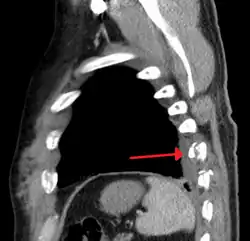

Plain X-rays often pick up displaced fractures but often miss undisplaced fractures.[13] CT scanning is generally able to pick up both types of fractures.[13]

Illustration showing rib fracture at 3rd, 4th and 5th rib -

Two broken ribs as seen on parasagittal CT